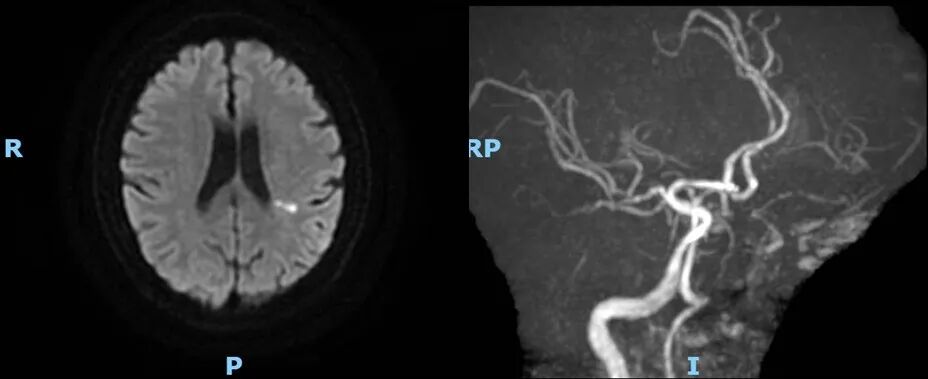

2022-07-21 颅脑MR。

导丝怎么扩【载药时代 球扩天下】NOVA DES®颅内药物洗脱支架在颈内动脉颅内段重度狭窄的应用二例!_https://www.jmylbn.com_新闻资讯_第25张

DWI

导丝怎么扩【载药时代 球扩天下】NOVA DES®颅内药物洗脱支架在颈内动脉颅内段重度狭窄的应用二例!_https://www.jmylbn.com_新闻资讯_第26张

MRA

重要影像结论:左侧额顶枕叶梗死灶。